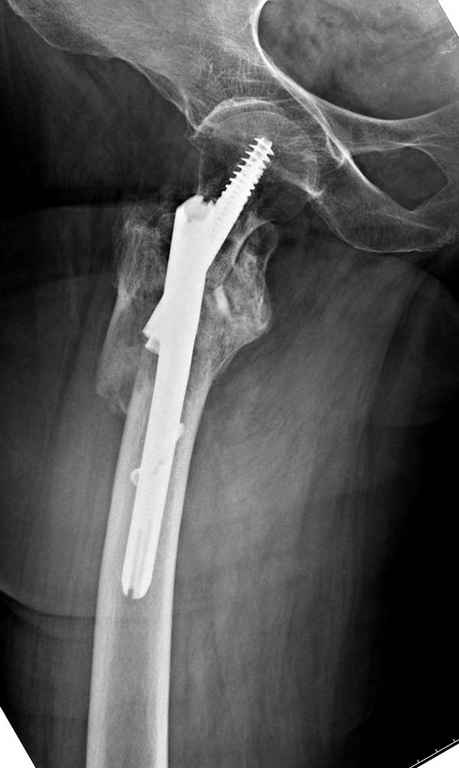

А так для лечения оскольчатых переломов подходят все методы, включая интра- и экстрамедуллярные в зависимости от опыта и наличия импланта.

Здесь пара похожих случаев.